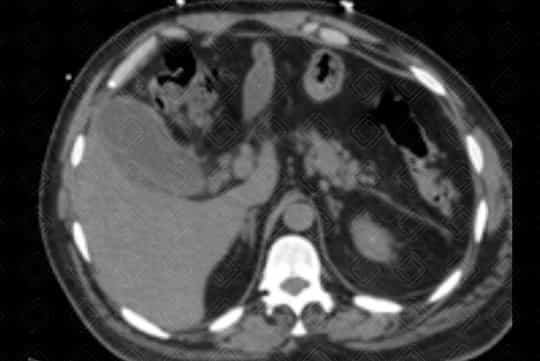

Descrição das figuras: Tomografia computadorizada de abdome com contraste venoso. Vesícula biliar contendo cálculo no seu interior, distendida, com espessamento parietal e densificação dos planos adiposos perivesiculares. Achados compatíveis com colecistite aguda.

• Tomografia computadorizada do abdome : Menos sensível quando comparado à ultrassonografia. Em alguns casos pode não visualizar o cálculo biliar. No entanto é excelente para a avaliação da inflamação perivesicular adjacente;